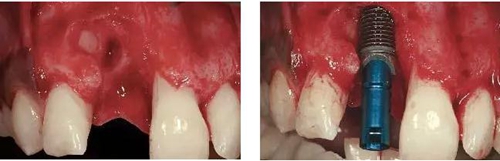

圖3、拔牙后看到更大范圍的骨缺損,并且缺損導(dǎo)致上頜側(cè)切牙根尖牙骨質(zhì)暴露,繼而存在術(shù)后由于軟硬組織退縮而帶來(lái)的美學(xué)風(fēng)險(xiǎn)。

圖4、植入的種植體,初始穩(wěn)定性很好,由于骨缺損范圍大,選擇潛入式愈合。

圖5、種植體完全位于拔牙窩骨壁包圍的范圍內(nèi),距離唇側(cè)骨板至少2mm。